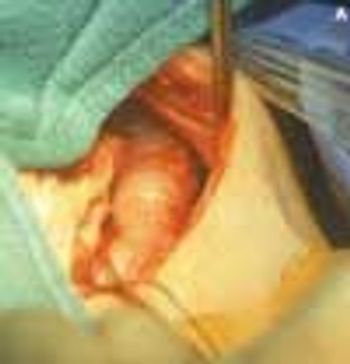

Severe pain in the scrotum during a soccer game sent a 14-year-old boy to his physician. The right testicle was swollen and exquisitely tender. On exploration, it was hemorrhagic and blue-black. A small incision in the tunica of the testis revealed arterial bleeding, which indicated that the testis was still viable. The right testicle was untwisted and fixed to the scrotum.